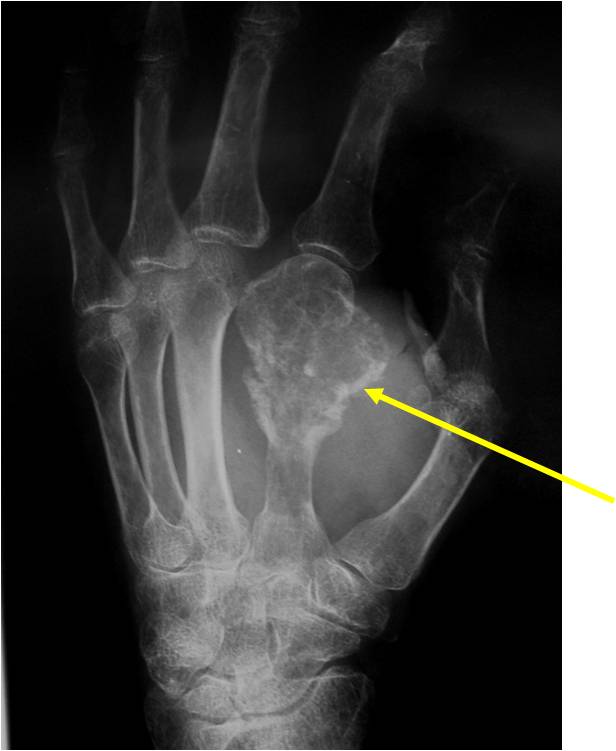

- 50% involve hands and feet (mostly phalanges)

- Localized, radiolucent defect usually with punctate calcifications

- Calcifications are stippled, punctate, popcorn like calcifications and “Ring and Arc” calcifications

- Grows eccentrically or concentrically (phalanges)

- Cortex may be scalloped and thinned in the phalanges

- Geographic lytic lesion

- Expansile remodeling with thinned cortex

- Chondroid matrix with calcifications in majority of tumors

- Digits: Impending or actual pathological fracture

- Intralesional curettage and bone graft or cement